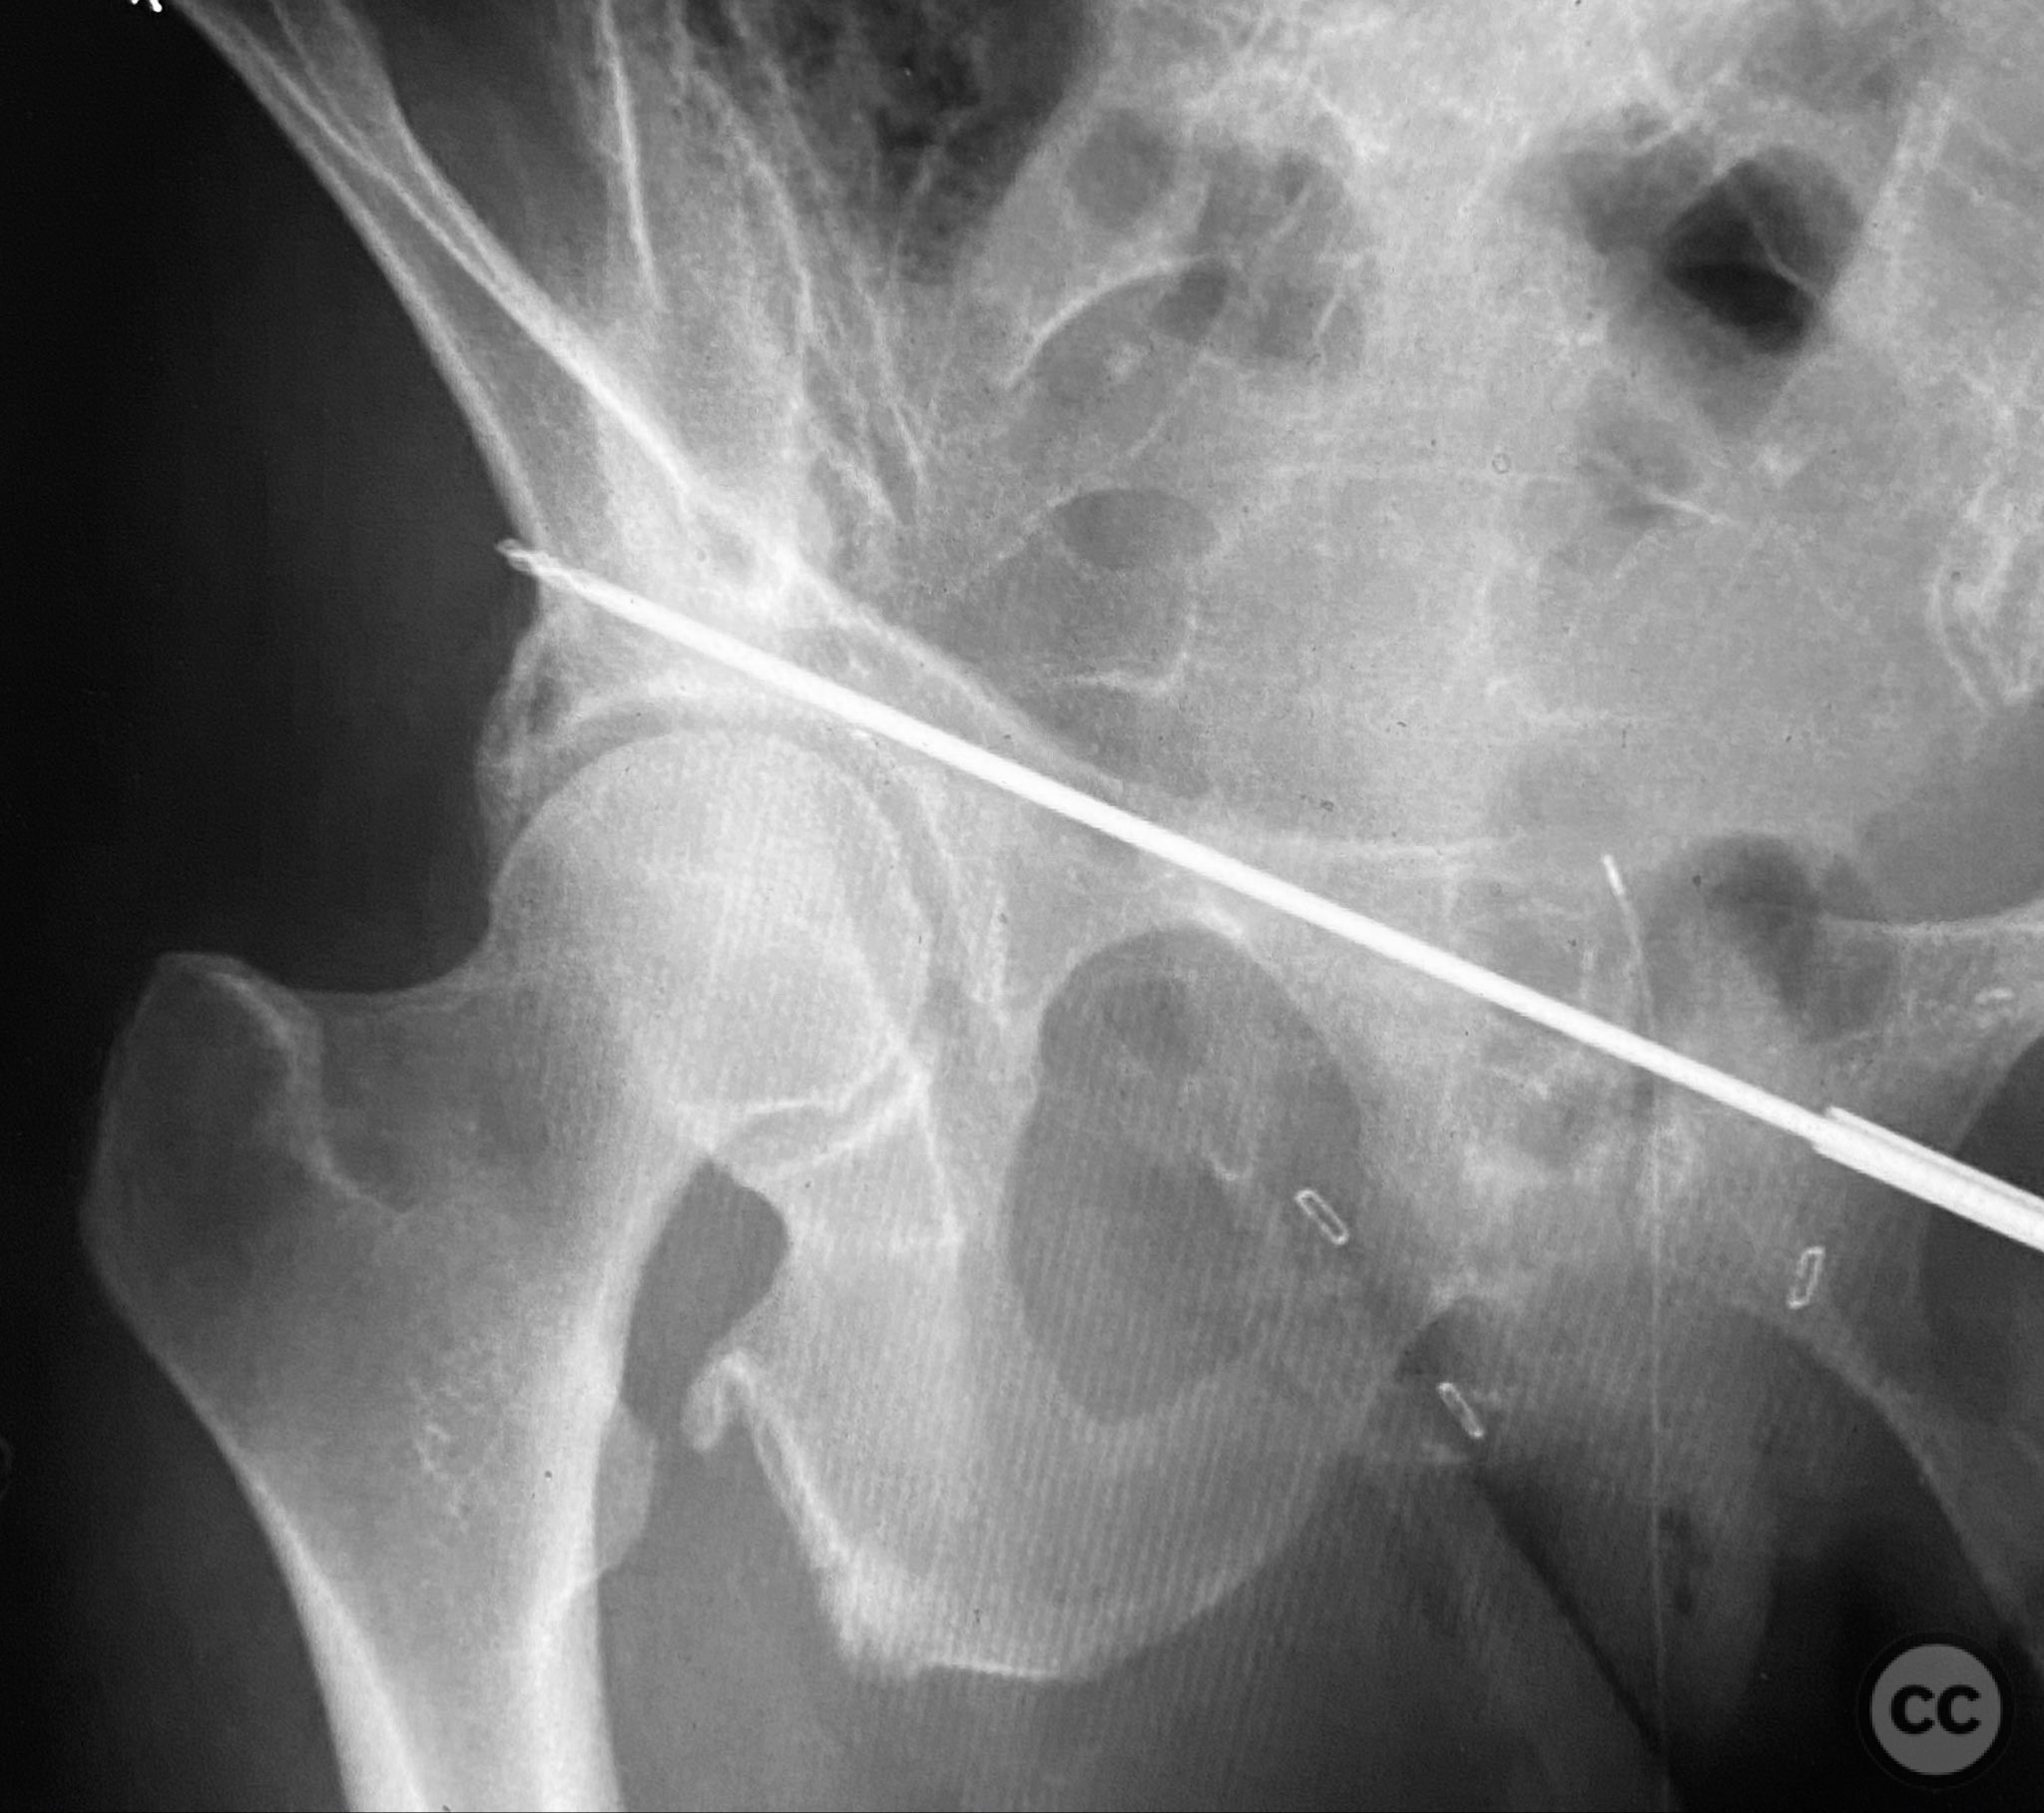

Anatomical surgical approach:  Pfannenstiel (transverse suprapubic) incision made approximately 2cm above the symphysis pubis. Dissection carried through subcutaneous tissue and rectus sheath, with blunt separation of rectus abdominis muscles to expose the symphysis pubis and superior pubic ramus. Periosteal elevator used for subperiosteal exposure of the superior pubic ramus, maintaining careful retraction of neurovascular structures.

Intraoperatively, a 3.5mm drill was used through a protective sleeve to initiate the screw pathway across the superior pubic ramus. Due to poor bone quality, a 2.5mm drill was subsequently employed; however, resistance was encountered as the drill tip engaged the dense cortical apex of the anterior acetabular wall. The drill became lodged in this region. To avoid drill breakage, manual extraction using pliers was considered; however, the surgeon elected to carefully deflect and advance the drill manually, successfully completing the pathway. Screw length was measured directly from the embedded drill tip. A 4.5mm cortical screw was then inserted trans-symphyseally along the prepared medullary canal, achieving stabilization of the unstable ramus fracture. Postoperative CT confirmed appropriate screw trajectory and demonstrated the dense cortical bone at the anterior acetabular wall where the drill tip had engaged.